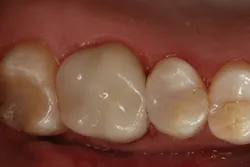

Figure 9: Completed restoration

The clinical case in Figure 3 illustrates a patient who presented with a large, failing restoration containing cracks and decay. The patient was interested in an all-ceramic restoration. Occlusion was checked with articulating paper prior to treatment with a CAD/CAM restoration (figure 4). All previous restorative materials were removed from the tooth (figure 5). The tooth was restored using Grandio Core Dual Cure (Voco) build-up material (figure 6). A crown preparation was completed for a chairside CAD/CAM crown using the CEREC system (Dentsply-Sirona). The material of choice for this restoration was IPS e.max CAD (Ivoclar Vivadent), which is seen in Figure 7 after milling and in precrystallization form. The restoration was tried in and then polished, glazed, and placed in the oven for crystallization. The internal surface was then etched with 4.9% hydrofluoric acid, rinsed, and then coated with a silane coupler to create an optimal surface for bonding with the resin luting agent. The tooth was isolated and cleaned prior to etching. Once etched, the adhesive bonding agent (Futurabond U) was activated to mix the two liquids within the single-dose blister package. The blister seal was broken with the bonding agent brush and the adhesive was applied and agitated for 20 seconds. The adhesive was lightly dried for five seconds and then cured with an LED curing light for 10 seconds. A dual-cured adhesive resin luting agent (Bifix QM) was dispensed into the crown with its automix syringe (figure 8). The crown was seated and excess cement was removed after a two-second light cure. The tooth was then flossed and occlusion was checked (figure 9). The patient was very satisfied with the final result.